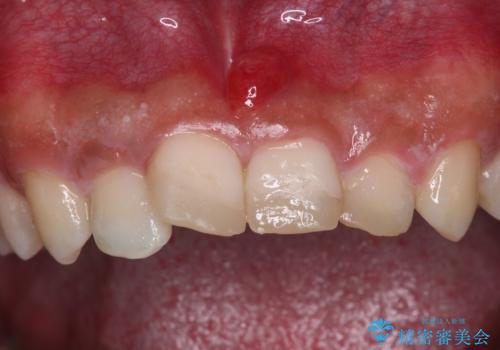

転んでぶつけて抜歯 前歯のオールセラミックブリッジ

- 酒席の後に転倒して前歯を損傷し、応急処置のみを受けてきたとのことで来院された患者様です。

損傷がひどく、前歯4本と広範囲であったため、症状やレントゲン写真、検査結果が一致せず、定期的に経過を見ながら診断していくこととしました。

右側前歯は歯根が短くなり、パンチング状に歯根に透過像が認められたため、予後不良と判断し抜歯することとしました。

当初のレントゲン写真では根尖部に骨透過像が認められた両サイドの2歯は、歯髄の正常な反応が認められたためそのまま保存し、左側前歯は歯髄が失活していたため根管治療を行うこととしました。

抜歯後の欠損部はブリッジにて補綴治療を行うこととしました。

事故直後のレントゲン写真では全ての歯の根尖部に骨透過像が認められましたが、治療後には全ての透過像がなくなっていました。

診断に2-3ヶ月かかりましたが、的確に診断を行うことができました。